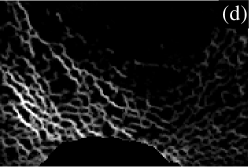

III.6 Illustration

To illustrate the analytical method, we now present the results in visual form for an enlarged region near the bottom (posterior) of the slice in Fig. 1. The enlarged region of the original image is shown in Fig. 3(a). Parts (b) to (e) of Fig. 3 show directional strand strengths, and part (f) shows the final node strength plot. Each directional strand strength plot shows the sum of two strand strengths at every pixel, in opposite directions: east/west; north/south; northwest/southeast; and northeast/southwest. In each of the directional strand strength plots, the strands in the given direction are shown with the highest intensity, but most of the trabeculae are still visible, even if faintly. In contrast, in the node strength plot (part (f)), most of the trabeculae are invisible. This is because of the subtraction of the minimum strength constant. In this example, there are almost no nodes in the right half of the image. This correctly describes the micro-architecture of the original image in that region, which contains many trabeculae but few that cross each other to make a lattice-like micro-architecture. The left half of the image contains many nodes. Notice that, in the node strength plot, the nodes seem to be thicker than in the original image. This is because the trabeculae in the original image are actually slightly thicker than they appear, the outer pixels being dimmer (i.e. lower CT values) and thus not easily registered by the eye. Since the outer pixels near the apparent nodes in the original image are almost as well-connected as pixels in the centres of the nodes, they have large node strengths, and are very visible in the node strength plot.